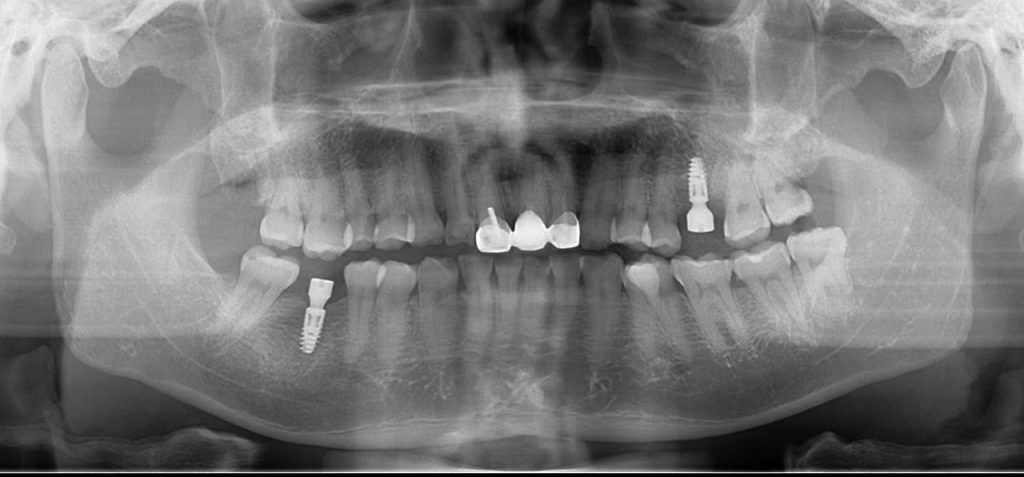

Trồng răng implant có đau không là một câu hỏi mà nhiều người băn khoăn trước khi quyết định thực hiện phương pháp này. Tuy nhiên, cảm giác đau thường liên quan đến từng cá nhân và cách thức thực hiện của bác sĩ.

Phẫu thuật cấy ghép: Quá trình cấy ghép răng implant bao gồm việc tạo một lỗ nhỏ vào xương hàm để đặt trụ implant, và quá trình này có thể gây cảm giác hơi khó chịu, nhưng bạn sẽ không cảm thấy đau nhờ thuốc tê.